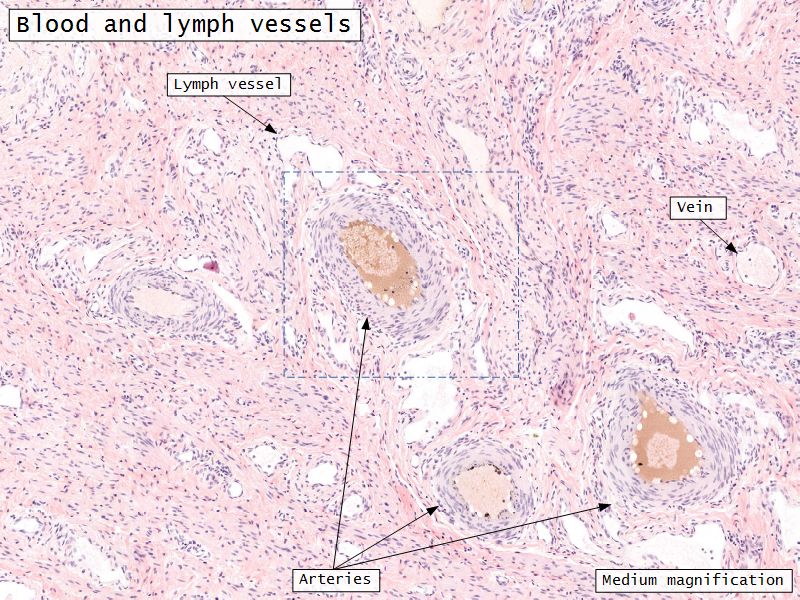

Medulla

- Blood vessels

- Hilus cells

- Stroma

Blood vessels

- Enter medulla at hilus

- Supply the cortex

- Epithelioid cells clump around blood vessels

Serosa

- Simple squamous epithelium

- Contains

- Blood vessels

- Lymphatics

- Nerves

Blood supply

- Originate from myometrium

- Helical arteries

- Extend into functional layer

- Straight arteries

- Terminate basal layer

Adventitia

- Fibroelastic connective tissue

- Fixes onto surrounding structure

- Blood vessels and nerves